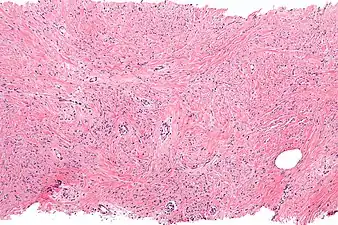

a)Mammary-type myofibroblastoma b) positive for CD34 c) and desmin

a)Mammary-type myofibroblastoma b) positive for CD34 c) and desmin Intermed. mag. Mammary myofibroblastoma

Intermed. mag. Mammary myofibroblastoma High mag. Mammary myofibroblastoma

High mag. Mammary myofibroblastoma

Medical imaging may suggest but cannot prove that a tumor is MFB. Mammography, computed tomography scans, and magnetic resonance imaging of mammary[1][12] and extramammary[1][13] MFB typically show well-defined and well-circumscribed tumors which in almost all cases have no calcifications; these results suggest that the tumor is not malignant but do not indicate which type it might be. The diagnosis of MFB depends on the microscopic histopathology (i.e. appearances after proper tissue preparation and staining) of its pre-surgery biopsied issues. As shown in the upper image and the two images in the Additional images section seen below, both mammary and extramammary MFB tissues contain spindle cells, variable numbers of adipocytes (i.e. fat cells) and broad sheets or, less often, thick bundles of collagen fibers.[5] About 4% of cases have an epithelial tumor cell-like morphology,[5] i.e. the tissues are composed predominantly of epithelioid cells variably mixed with a minority (10% to 40%) of round, polygonal, and spindle-shaped cells.[19] Unlike malignant tumors, MFB tumors do not have: a) atypical cells except in the rare cases which contain small clumps of multinucleated cells; b) rapidly proliferating cells as defined by measuring the proliferative index (i.e. fraction of cells undergoing mitosis); or c) areas of necrosis (i.e. areas of dead or dying cells).[16] Microscopy of tumors in the spindle cell lipoma tentative variant of MFB show a mixture of mature fat cells, ropey collagen, and spindle cells in a myxoid (i.e. background connective tissue that stains blue or purple rather than the red of normal connective tissue) matrix.[18] The blood vessels in these tumors often appear hyalinized.[16] Tumor tissues in the tentative cellular angiofibroma variant of MFB contain spindle cells in all cases, fat cells in ~50& of cases, mast cells, peri-vascular infiltrates of lymphocytes, pleomorphic cells in some cases, and cells with some features of the malignant sarcoma cells in sarcoma tumors in rare cases. (The presence of these sarcoma-like cells does not seem to impact the prognosis of this variant.) All of these cells are in edematous-to-fibrous stromatous tissue.[16]